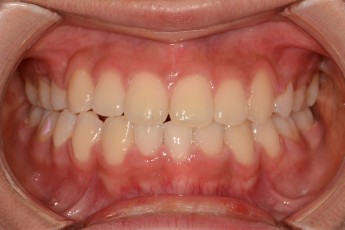

BEFORE & AFTER

- 돌출입교정